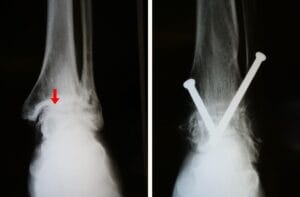

During arthroscopy, your surgeon inserts a small camera, called an arthroscope, into your foot or ankle joint. The camera displays pictures on a television screen, and your surgeon uses these images to guide miniature surgical instruments. Because the arthroscope and surgical instruments are thin, your surgeon can use very small incisions (cuts), rather than the larger incision needed for a traditional, open surgery. Arthroscopic surgery is most effective when pain is due to contact between bone spurs and the arthritis has not yet caused significant narrowing of the joint space between the bones. Arthroscopy can make an arthritic joint deteriorate more rapidly. Removing bone spurs may increase motion in the joint, causing the cartilage to wear away quicker. Arthrodesis (fusion). Arthrodesis fuses the bones of the joint completely, making one continuous bone out of two or more bones. The goal of the procedure is to reduce pain by eliminating motion in the arthritic joint. During arthrodesis, the doctor removes the damaged cartilage and then uses pins, plates and screws, or rods to fix the joint in a permanent position. Over time, the bones fuse, or grow together, just like two ends of a broken bone grow together as it heals. Since the bones no longer move, there should not be any more pain.

Screws are used to fuse the bones of the hindfoot and prevent painful motion.

Reproduced and modified from Abdo RV, Iorio LJ: Rheumatoid arthritis of the foot and ankle. J Am Acad Orthop Surg 1994;2:326-332.

(Left) X-rays shows ankle arthritis. Joint spacing narrow (arrow) has resulted in bone rubbing on bone. (Right) A different arthritic ankle after treatment with arthrodesis. Screws are used to hold the bones in proper alignment until the fusion is complete.